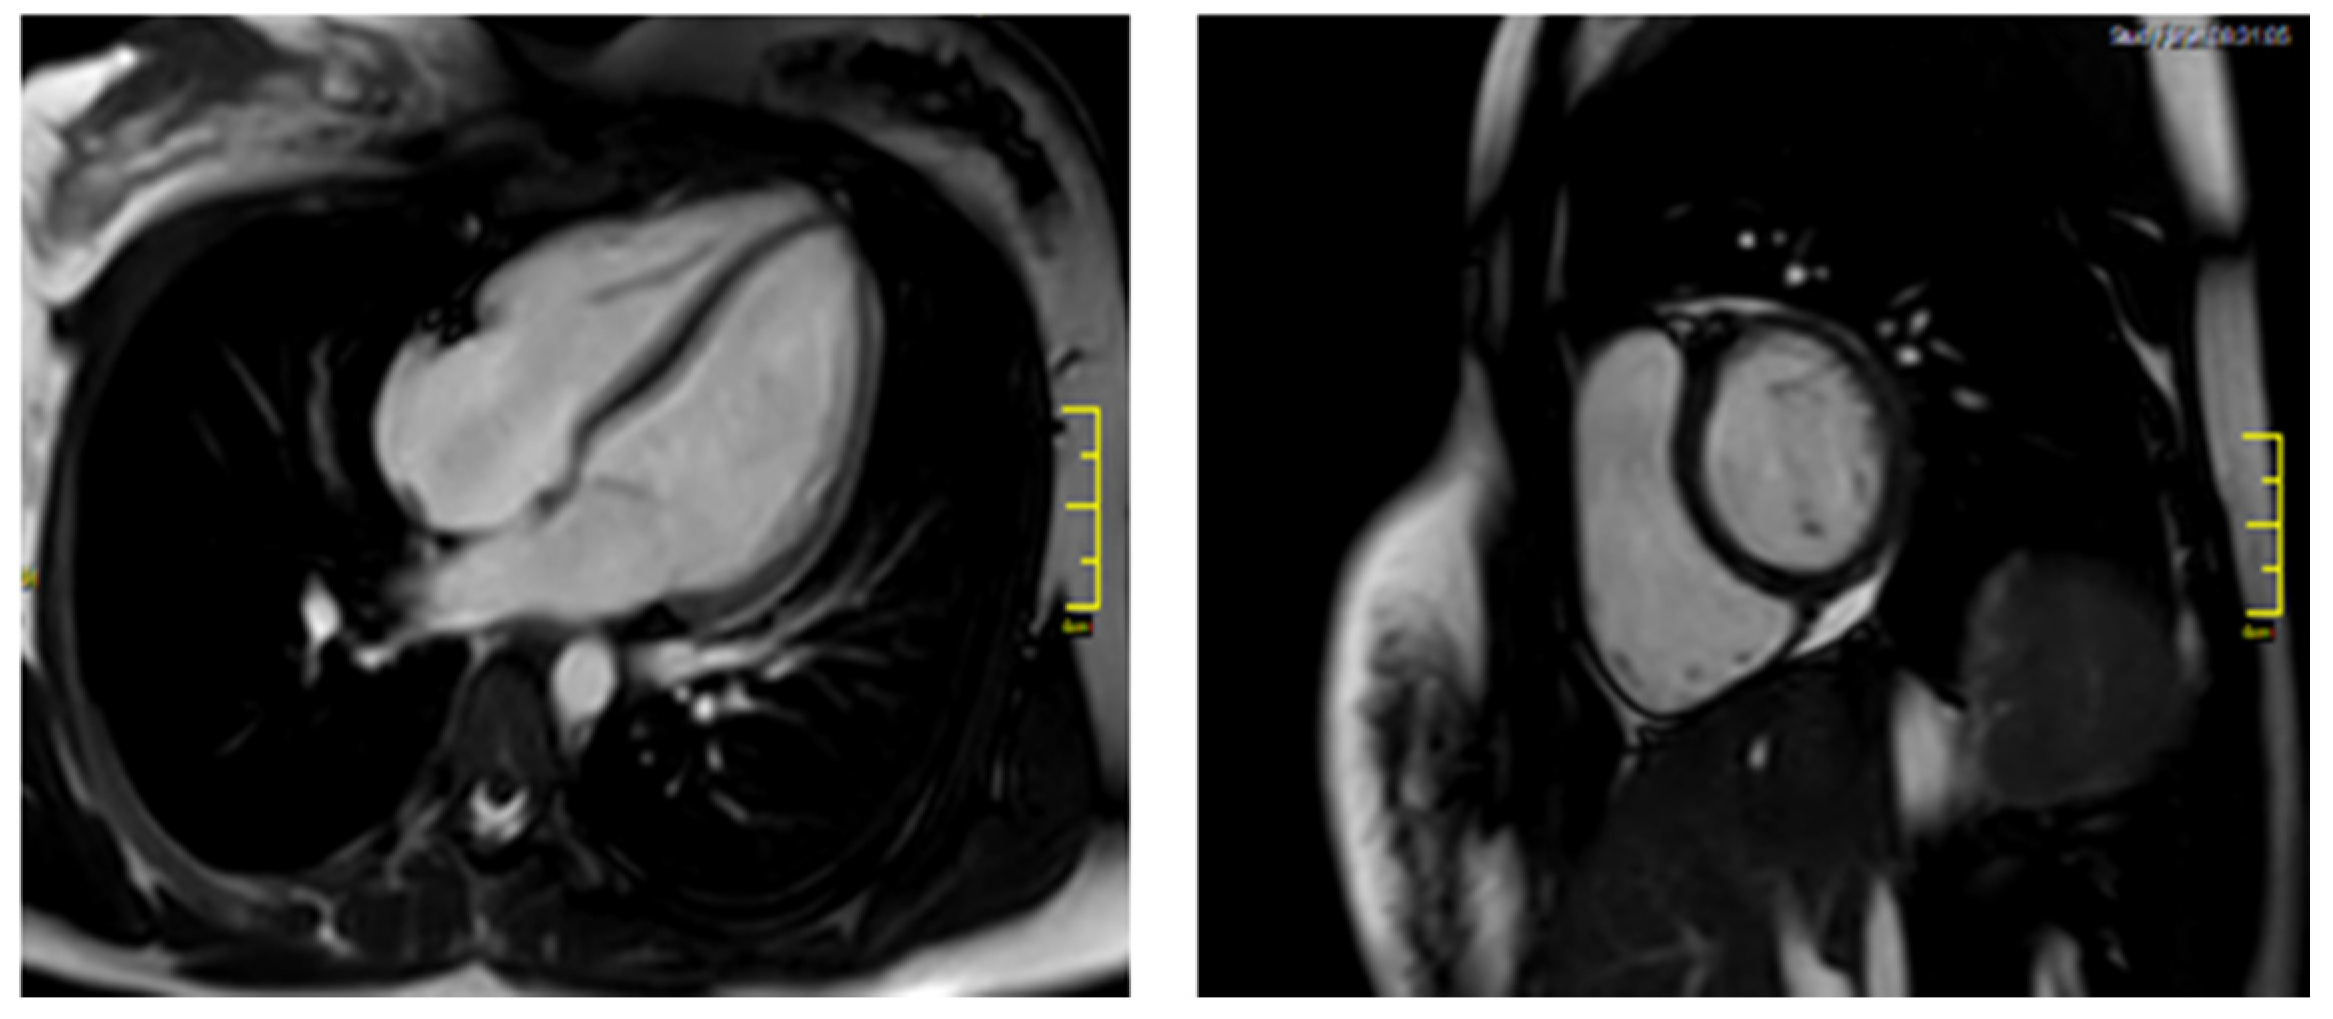

On the follow-up appointment, one month after discharge, patient’s electrocardiographic and echocardiographic evaluations as well as serum cardiac biomarkers were normal. Additionally, the CMR findings did not demonstrate any markers of myocardial inflammation and necrosis (Figure 3). The Luise Lake Criteria for acute myocarditis were not fulfilled by that time as no high signal intensity on T2-weighted imaging, increased T2 and T1 times, myocardial thickening, or rapid uptake (early gadolinium enhancement) of contrast were revealed [3]. Subsequently, antiarrythmic medication was discontinued.

Figure 3.

Follow-up CMR.